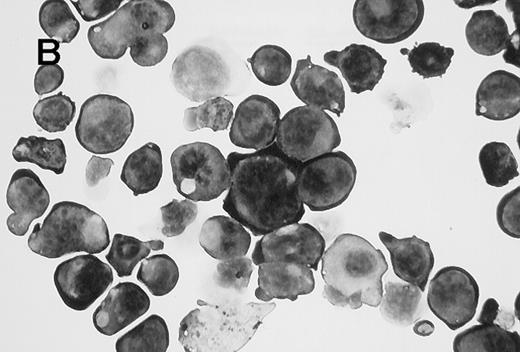

Wright-Giemsa staining of CD41brightc-kitbright cells revealed lymphocyte-sized mononuclear cells with a large nucleus-cytoplasm ratio (Figure2A). After incubation of these cells with TPO for 2 days, they became large cells with complex nuclei as shown in Figure 2B. Acetylcholinesterase staining verified that 77% of the cells were megakaryocytes by this criteria. Flow cytometric analysis showed that the starting CD41bright c-kitbrightcells were diploid; after a 2-day incubation with TPO, the cells became highly polyploid (Figure 3).

Appearance of CD41brightc-kitbright cells.

(A) Cells sorted in the CD41bright c-kitbrightfraction were stained with Giemsa following cytocentrifugation. (B) CD41high c-kithigh cells after incubation with murine TPO (25 ng/mL) for 2 days. The magnification of the two images is similar (×1000).